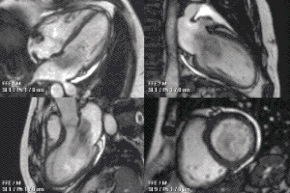

Congenital heart defects are the most common type of major birth defect. Accurate diagnosis is essential for the development of appropriate treatment plans. CMR can provide comprehensive information about the nature of congenital hearts defects in a safe fashion without using x-rays or entering the body. It is rarely used as the first or sole diagnostic test for congenital heart disease.

Rather, it is typically used in concert with other diagnostic techniques. In general, the clinical reasons for a CMR examination fall into one or more of the following categories: (1) when echocardiography (cardiac ultrasound) cannot provide sufficient diagnostic information, (2) as an alternative to diagnostic cardiac catheterization which involve risks including x-ray radiation exposure, (3) to obtain diagnostic information for which CMR offers unique advantages such as blood flow measurement or identification of cardiac masses, and (4) when clinical assessment and other diagnostic tests are inconsistent. Examples of conditions in which CMR is often used include tetralogy of Fallot, transposition of the great arteries, coarctation of the aorta, single ventricle heart disease, abnormalities of the pulmonary veins, atrial septal defect, connective tissue diseases such as Marfan syndrome, vascular rings, abnormal origins of the coronary arteries, and cardiac tumors.

Enlarged right ventricle with poor function in a patient with repaired tetralogy of Fallot by CMR